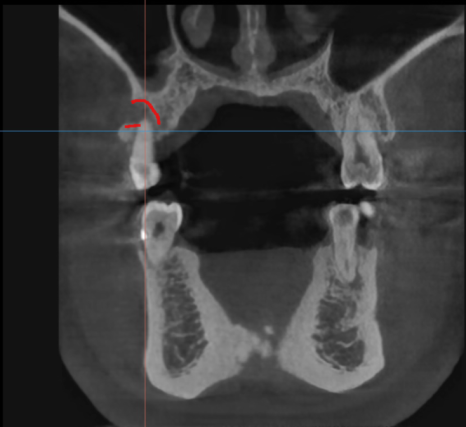

CT 상에서도 뼈가 녹아 치아가 붕~ 떠있는 것을 볼 수 있고요

이럴 때는 발치 후 염증을 깨끗하게 제거

제 2의 치아인 임플란트 식립을 해줍니다.